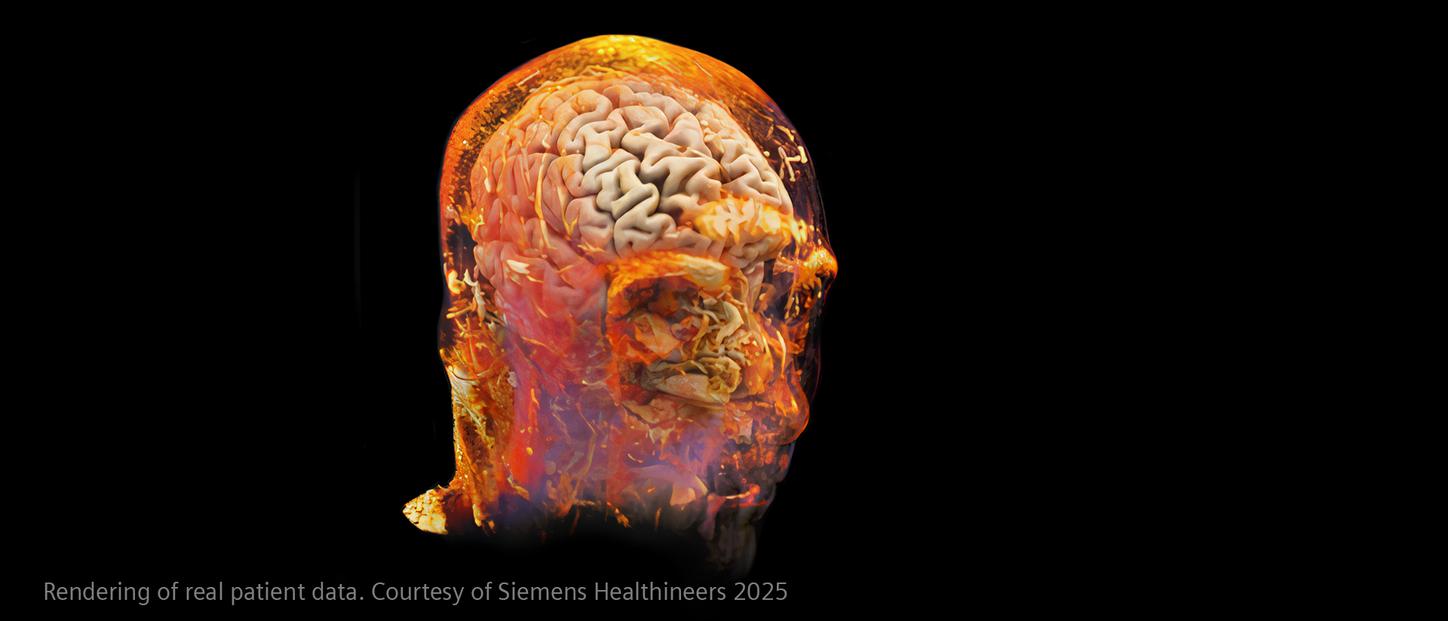

How advanced imaging and AI transform stroke workflow

In stroke care, time is brain. Rapid and accurate imaging is crucial to assess the extent of brain injury and guide immediate treatment. Angiography, MRI, CT, ultrasound, and lab diagnostics are essential tools in identifying stroke type, location, and severity. Advances in imaging technology now allow for even faster acquisition, improved resolution, and enhanced visualization of brain tissue and blood vessels. Innovations such as perfusion imaging, real-time vascular mapping, and AI-assisted diagnostics are transforming stroke workflows and enabling precise, timely interventions.